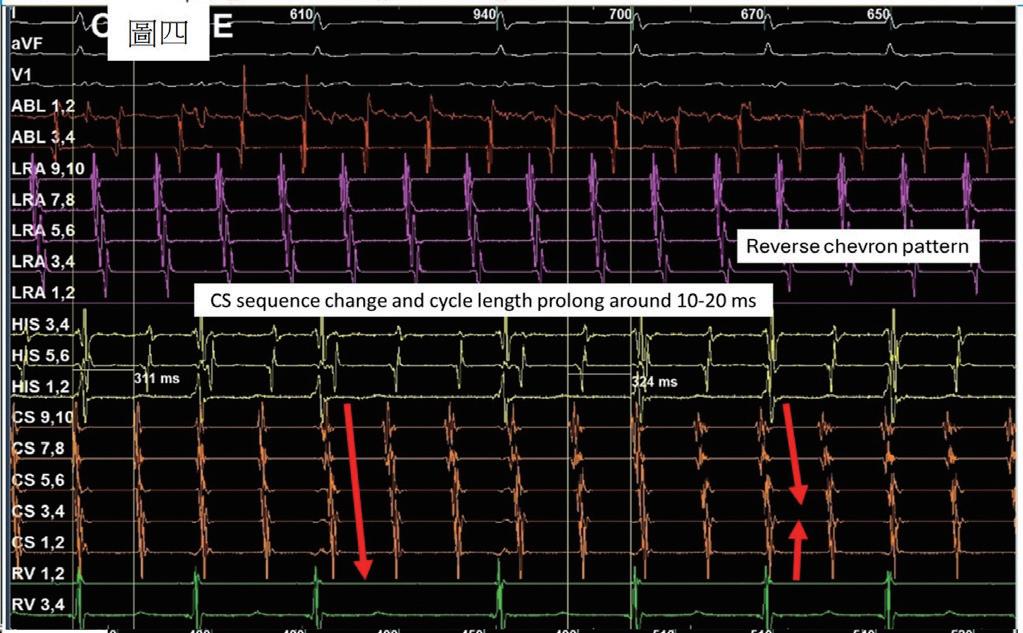

一位 76 歲女性,有高血壓以及陣發性心房顫動病史,規律於心臟科門診服用抗心律不整藥物 (flecainide) 以 及抗凝血劑 (apixaban) 以控制慢性病。然而,病人最近數月來感到間歇性胸悶與心悸,且症狀逐漸加重。經血 管介入專家排除冠狀動脈狹窄阻塞之問題後,判斷此病人之不適與多種嚴重心律不整有關 ( 如圖一與圖二 ) ,包 含可能源自於左心房的心房撲動 (atypical atrial flutters) 。經詳細解釋與討論,病人決定入院接受電氣生理檢查 與電氣燒灼治療。術前電腦斷層顯示左心房及左心耳無血栓,左心房有擴大 ( 約為 160 毫升 ) 。手術當日,病人心 律為 counter-clockwise isthmus-dependent atrial flutter( 如圖三 ) ,利用 entrainment method ,冠狀竇近端比遠端更 近 flutter circuit , 3 維傳播路徑圖為逆時針旋轉路徑。但是在 cavo-tricuspid isthmus 阻斷後, flutter 並未停止,發 生了訊號序列以及 cycle length 的變化,此時右側心房沒有辦法找到合適 entrainment 位置,經兩心房 3 維傳播路 徑圖判定病人之心律不整已轉變為源自左心房後壁之 atypical atrial flutter ,但是在左心房後壁阻斷後, flutter circuit 和 cycle length 仍不斷改變。在左心房經歷如同警匪追逐戰一般的多次阻斷以及訊號序列轉變後 ( 如圖四至 圖六 ) ,終於在冠狀竇 (coronary sinus) 遠端完成此病人的心律不整電氣燒灼手術 ( 如圖七 ) ,且無法再誘發。此病 人之心房撲動訊號序列變化與燒灼相關整理如圖八。術後病人恢復良好,胸悶心悸感已完全消除,固定於門診 領取抗凝血劑與低劑量抗心律不整藥物持續服用併追蹤。

(圖四)、 病人接受cavo-tricuspid isthmus阻斷後發生 第一次sequence change。病人在CS的訊號序 列呈現“reverse chevron pattern”。而且右 心房無法順利 entrainment 。於是進行心房 中膈穿刺,前往左心房繼續治療心房撲動。

(圖五)、 Mapping後判斷可能之critical isthmus位 於right superior pulmonary vein開口之後 側與前側。針對這兩個位置電燒後,發 生第二次訊號序列變換,轉變為CS 1,2往 CS 9,10之走向。